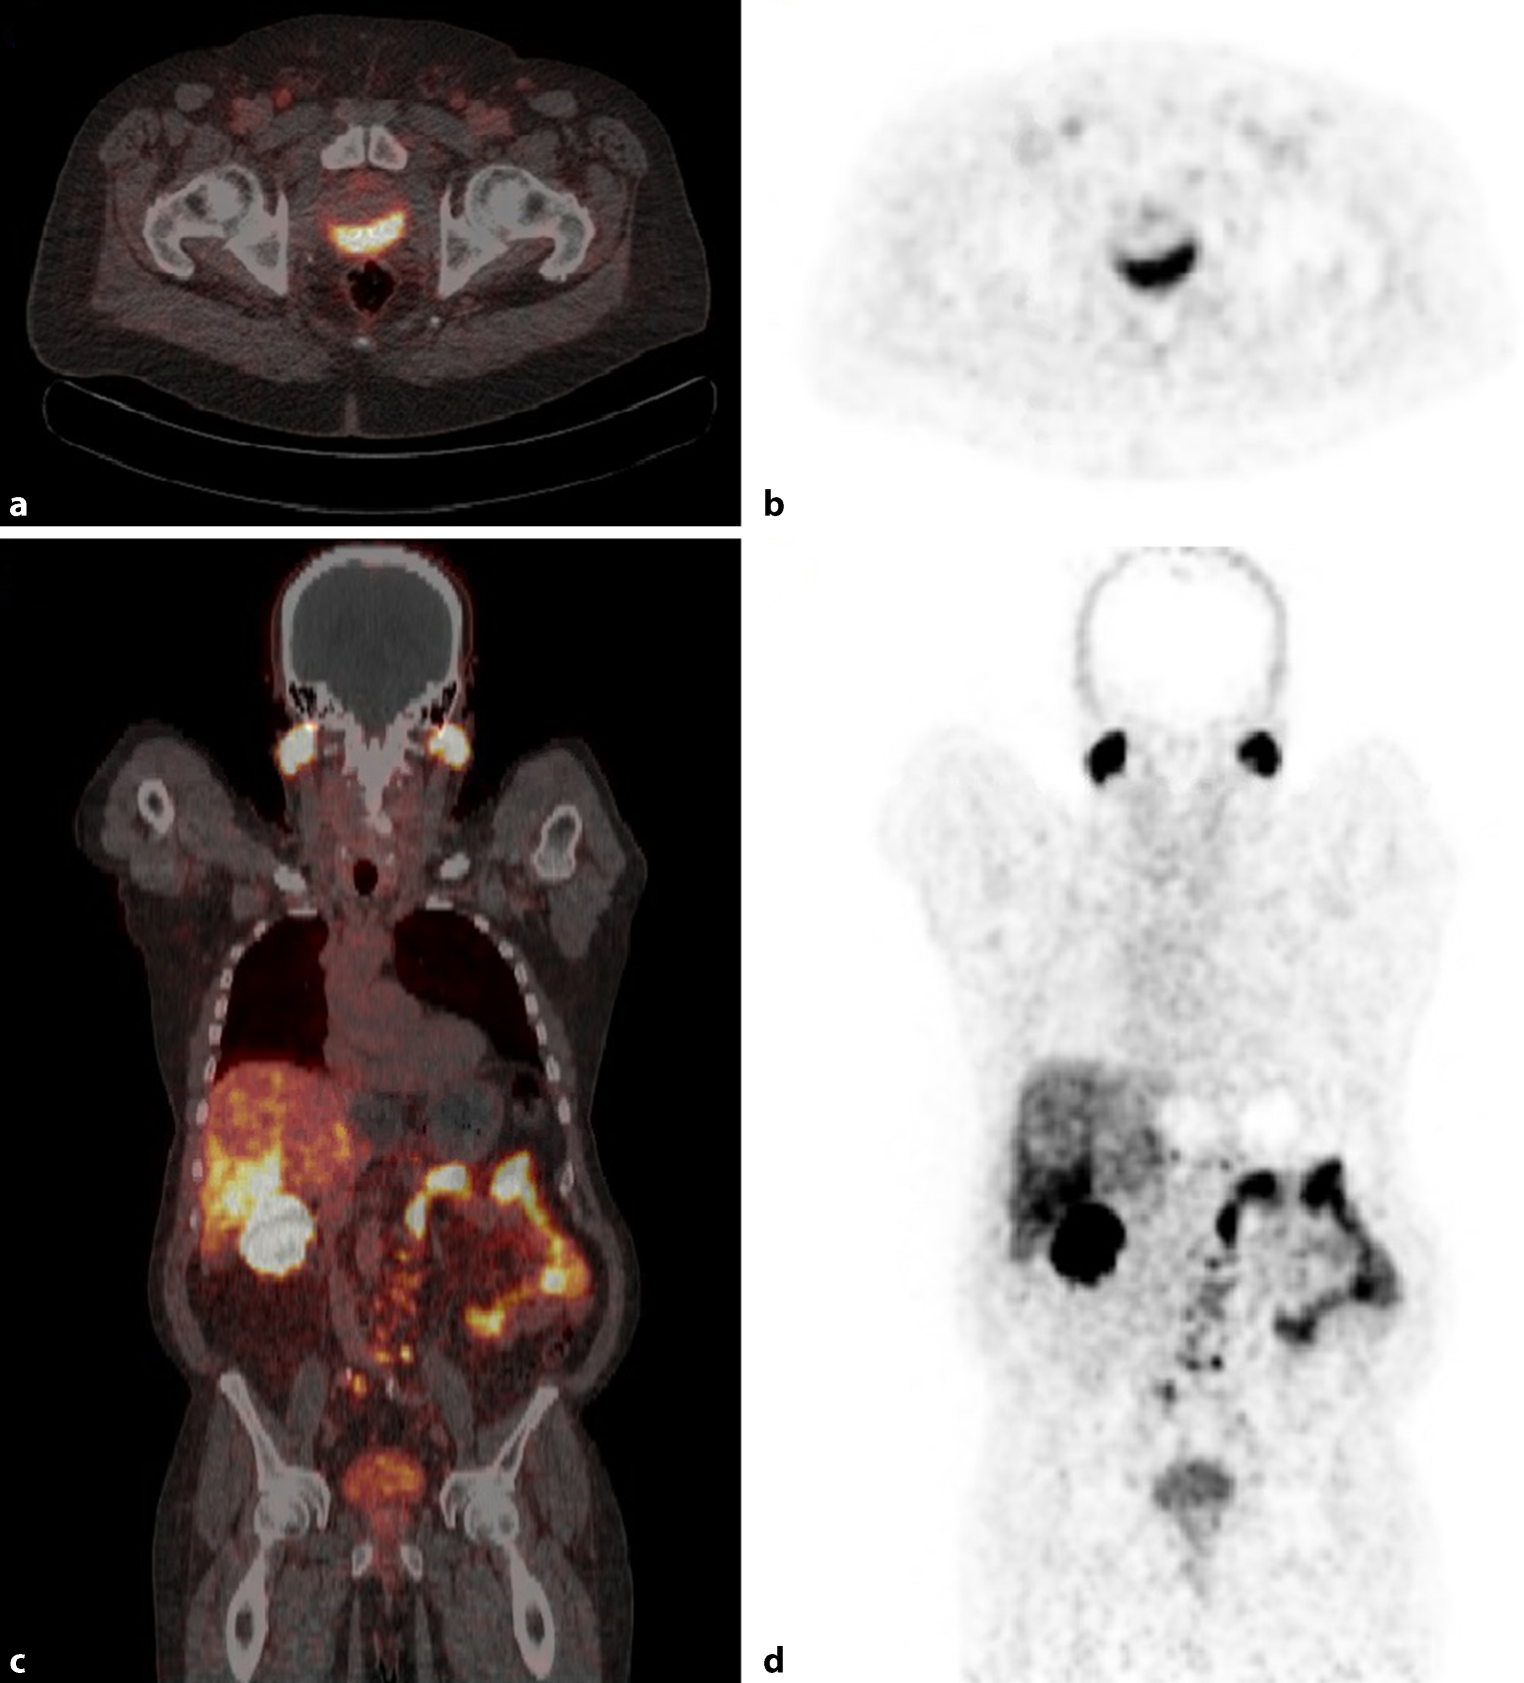

The PEPPER-study initiated by the University Medical Center Utrecht in the Netherlands was neither included in the review of Luiting et al. [26], nor in the systematic review of Hope et al. [20]. This was a prospective study evaluating the diagnostic accuracy of 68Ga-PSMA PET/CT for lymph node detection in primary staging in men with PCa with histopathology as a reference. Patients where included if they had newly diagnosed prostate cancer, negative skeletal scintigraphy, >10% risk for lymph node metastasis following (MSKCC)-nomogram and were eligible for an ePLND. A total of 103 patients where included. In six patients ePLND was canceled, because of 68Ga-PSMA PET/CT findings (i.e. PET positive distant lesions) illustrated in Fig. 4. A patient-based sensitivity and specificity of respectively 41.5% (95% CI 26.7–57.8) and 90.9% (95% CI 79.3–96.6) was found for detecting lymph node metastasis, and positive and negative predictive values of 77.3% (95% CI 54.2–91.3) and 67.6% (95% CI 55.6–77.7), respectively. Furthermore, a template-based (i.e. left/right and lateral/medial of the external iliac artery) sensitivity, specificity, PPV and NPV of 35.1% (59% CI 23.2–48.9), 96.4% (95% CI 93.5–98.1), 64.5% (95% CI 45.4–80.2) and 89.0% (95% CI 85.0–92.0), respectively, was observed [27].

Fig. 4

Case description. Transversal (a) and frontal (c) fused 68Ga-PSMA-PET/CT and transversal (b) and frontal (d) PET images of a 80-years old man with cT3a, Gleason 4 + 4 = 8 PCa (initial PSA-level of 33 ng/ml) and considered candidate for ePLND (MSKCC-nomogram: 77% risk of lymph node involvement). 68Ga-PSMA-PET/CT showed PSMA avid disease in the prostate region (a,b), as well as extensive bilateral (extra-) pelvic lymph node involvement (c,d). During the post-PET tumor board meeting, it was decided to cancel ePLND and start androgen deprivation therapy, followed by a PSA-decline to 0.24 ng/ml